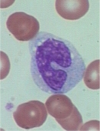

monocyte

19

Q

A

monocyte

20

Q

A

monocyte

21

Q

A

monocyte